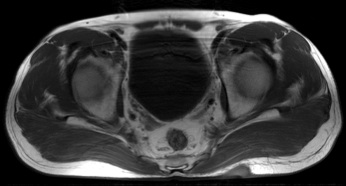

Figure 3 for case Hidradenitis suppurativa

Figure 3